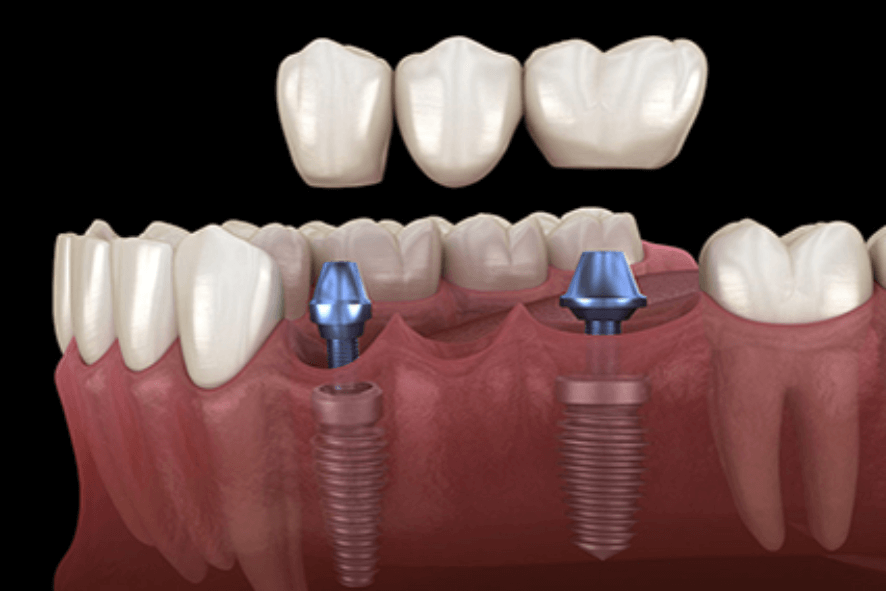

Ponte fixa sobre implante

Substitui vários dentes ausentes de uma vez, fixada em implantes para estabilidade e durabilidade.

👉 Oferece segurança, devolve a mastigação de forma eficiente e ajuda a manter a estética do sorriso em casos de múltiplas perdas.